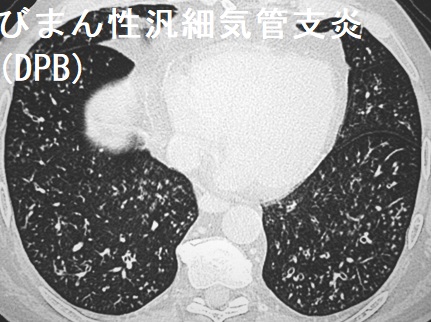

びまん性汎細気管支炎(DPB)のCT画像は、小葉中心性の小粒状影と線状影、気管支壁の肥厚が特徴です。(Eur Respir J. 2006 Oct;28(4):862-71.)

甲状腺分化癌(乳頭癌濾胞癌)の肺転移と比べ、粒が小さいです。

びまん性汎細気管支炎(DPB)